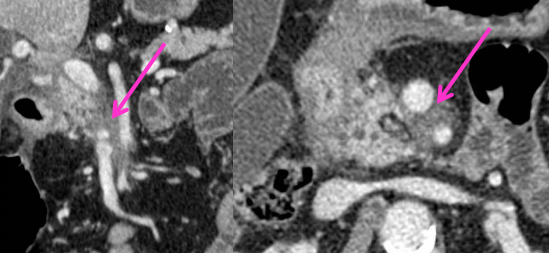

- Infiltration artérielle: <180° vs >180° et cranio-caudalement >2cm vs <2cm

- Infiltration veineuse: Contact, engainement, sténose, occlusion

- Infiltration de la lame rétroporte (entre l’AMS et l’uncus)

Lame rétroporte